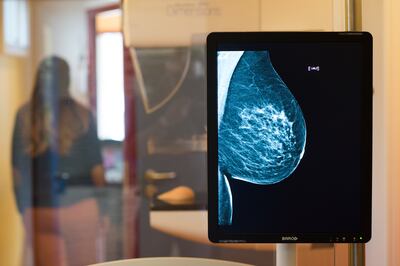

Aún no existen realmente alternativas a la mamografía. Por el momento no pueden ser reemplazadas por ningún otro tipo de procedimiento, dice Weg-Remers, “pero las sonografías y las resonancias magnéticas son importantes para completar la imagen”, apunta.

Actualmente también existe la tomografía computarizada de mama, una forma de diagnóstico que está siendo implementada en pacientes desde hace pocos meses, observa Karsten Ridder, un especialista en Radiología que trabaja en la ciudad de Dortmund.

La tomografía computarizada genera imágenes de alta resolución en 3D sometiendo a la persona a una muy baja radiación, explica Ridder, que realiza este tipo de estudios. “Queda claro el contraste del epitelio glandular y las calcificaciones”, indica, sin que la mama deba ser “comprimida”.

Susanne Weg-Remers también mira con buenos ojos este tipo de estudio. “Como no aplasta la mama, permite determinar con mayor precisión de qué zona sería mejor extraer una muestra”, explica. De todos modos, la especialista también advierte que la tomografía computarizada de mama aún está en fase experimental. En Alemania suele ser utilizada en investigaciones y estudios específicos llevados adelante en hospitales universitarios.